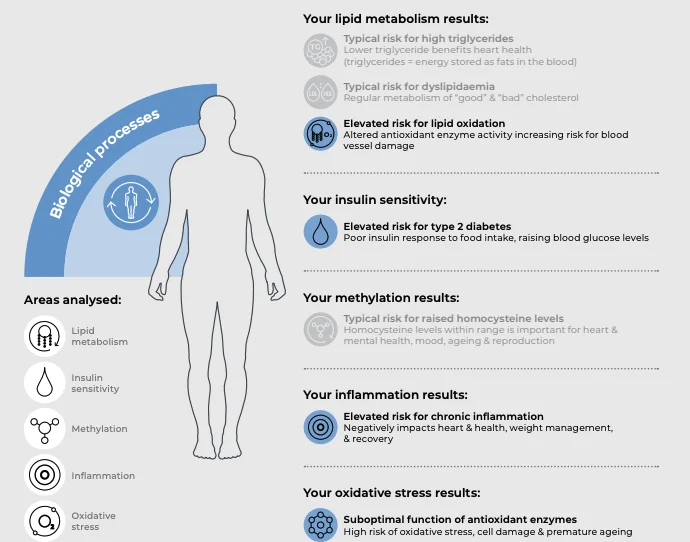

We offer five key tests to see what groups you fall into. These genes are known to affect:

Your individual sensitivity to anabolic steroids

AR - CAG repeats

How fast your body naturally breaks down steroids

CYP3A4*22

Your ability to convert androgens (male hormones) to oestrogens (female hormones)

CYP19A1

Your natural ability to excrete steroids

UGT2B17

Your ability to convert testosterone into a more active hormone.

SRD5A2